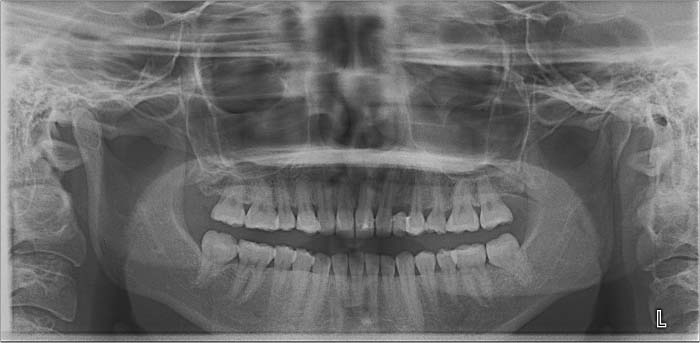

主訴 噛み合わせが悪い

期間 約2年2ヶ月

治療内容 ①スプリントを装着

②副子を装着

③2024年4月 口腔内反映開始

④副子を入れた状態の所まで咬合を挙上

(バイトアップ)

⑤2024年5月 上顎前歯部8本へ仮歯(TEK)

を装着

初診日 2023年10月12日